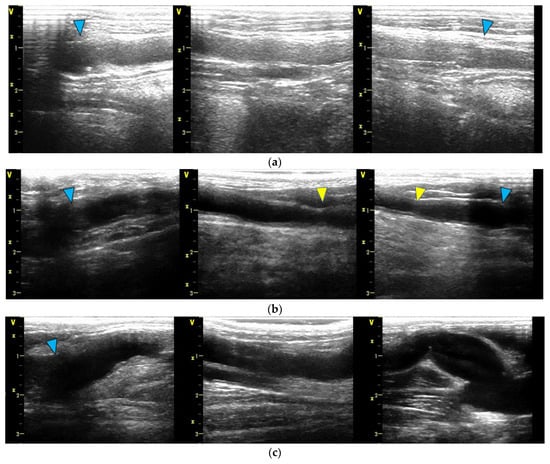

3.3. Histological Evaluation